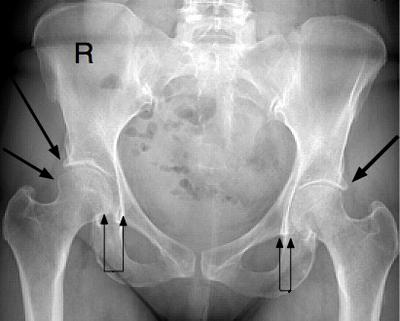

I have severe disc degeneration due to hard work, and heavy load carrying since the age of 14, I am now 69.

I have a left hip resurface, of 20 years standing.

My hips give me severe pain, and I am unsure as to its cause; could it be my nerves being pinched by the disc degeneration?

My left hip pains as much as the right, yet it is steel.